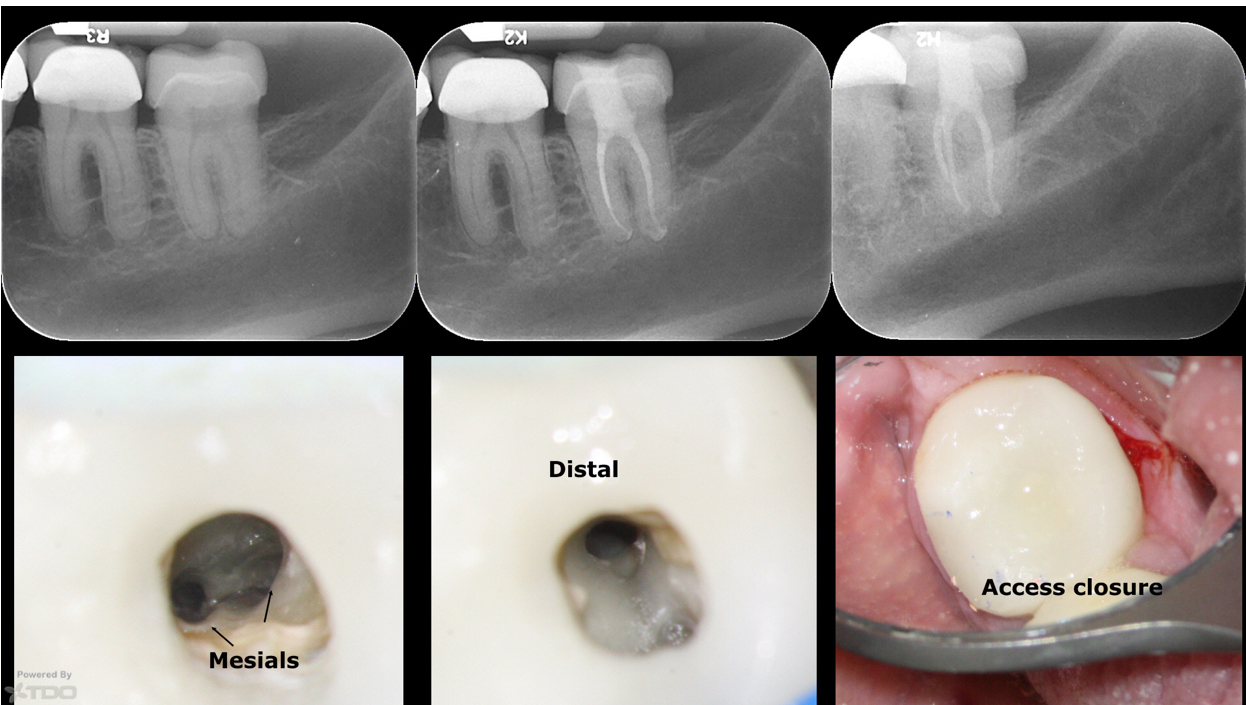

Conservative access

Heat treated files allow for conservative access in an area where a larger access would otherwise be needed.